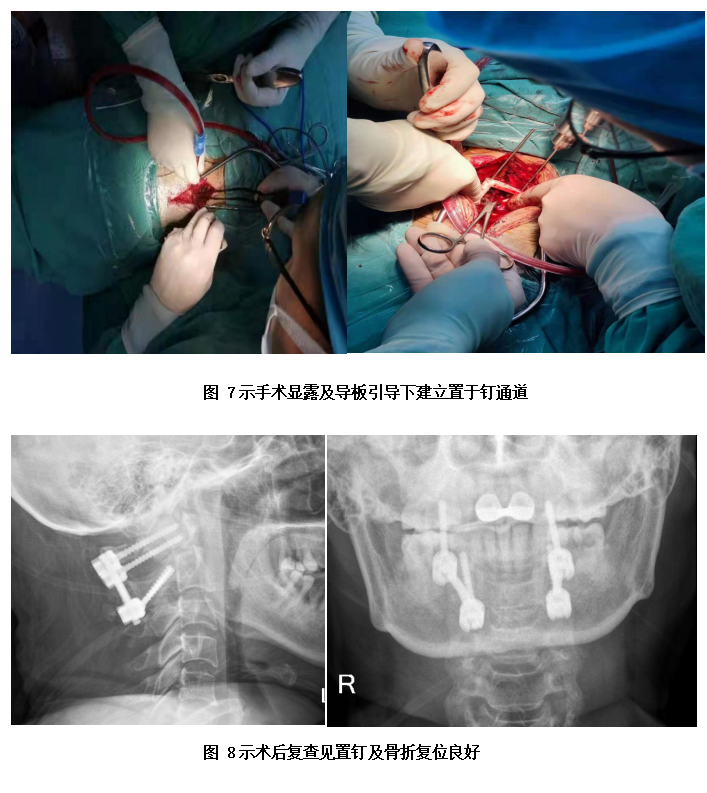

当充分完成术前准备后,于上月下旬,在麻醉科、手术室等医务人员的密切配合下,周医师及陈医师上台为杨阿姨实施了该手术。经过精心操作和不懈努力,成功为患者行了3D打印导板引导下的颈椎后路寰枢椎椎弓根螺钉内固定及取髂骨寰枢植骨融合术,术中患者出血少,手术取得圆满成功。